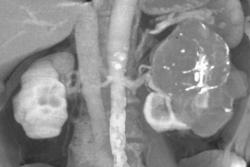

Late Phase Renal Cell Carcinoma